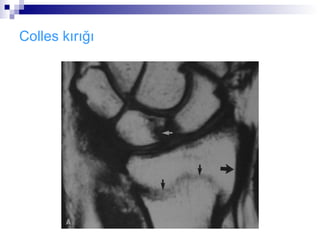

Colles kırığı

Die punch fraktürü:

   Kırık hattı radioulnar

ve radiokarpal ekleme

uzanabilir.(die-punch

kırığı)

   Ulnar styloid kırığı

sıklıkla görülür